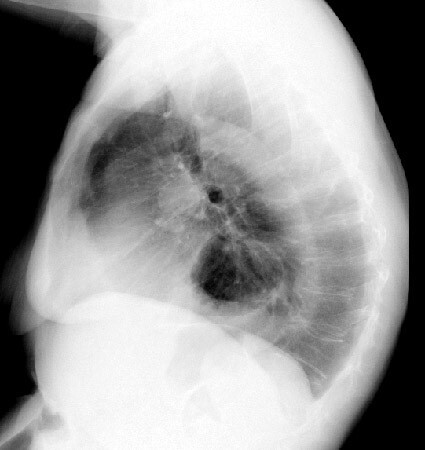

hiatal hernia

A

-A hiatal hernia occurs when the upper part of the stomach, which is joined to the esophagus moves up into the chest through the diaphragm.

-It is common and occurs in about 10% of pts

-SX:

-heartburn

-sudden regurgitation

-belching

-pain on swallowing hot fluids

-feeling a food sticking in the esophagus

-MC in overweight middle-aged women and elderly people.

-It can occur during pregnancy.

-dx confirmed by barium swallow, radiographs or endoscopy.